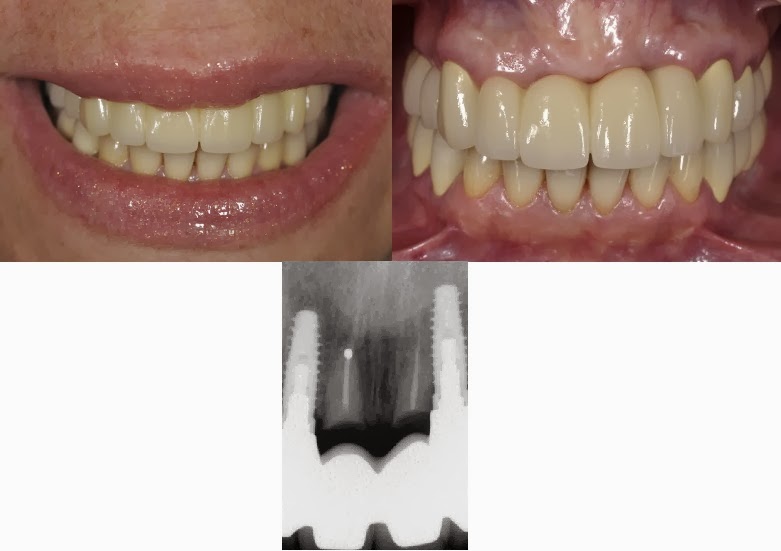

#11 This needs replacemtn to the exact same degree the authors need to write this article. They couldn’t find decay to replace or a broken tooth? I’ll see 100 teeth worse than that by noon on any given day and not even think about touching it. Total over treatment.